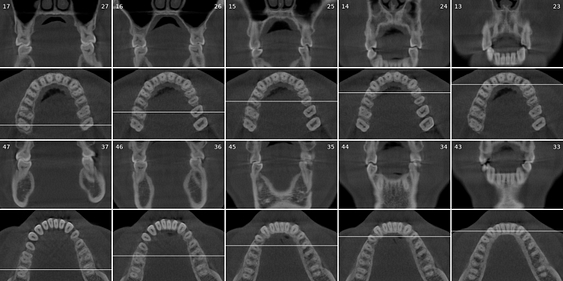

Cross-sectional and coronal views of teeth show torque and buccolingual relationships such as crossbite.

Tooth number is selected to analyze the root canal morphology within the CBCT radiograph.

Sagittal and coronal slices and highlighting the angle/curvature/length of the canals.

A single-third molar is selected to evaluate for extraction.

Generates slices in 3 directions and highlights the position of the inferior dental canal.